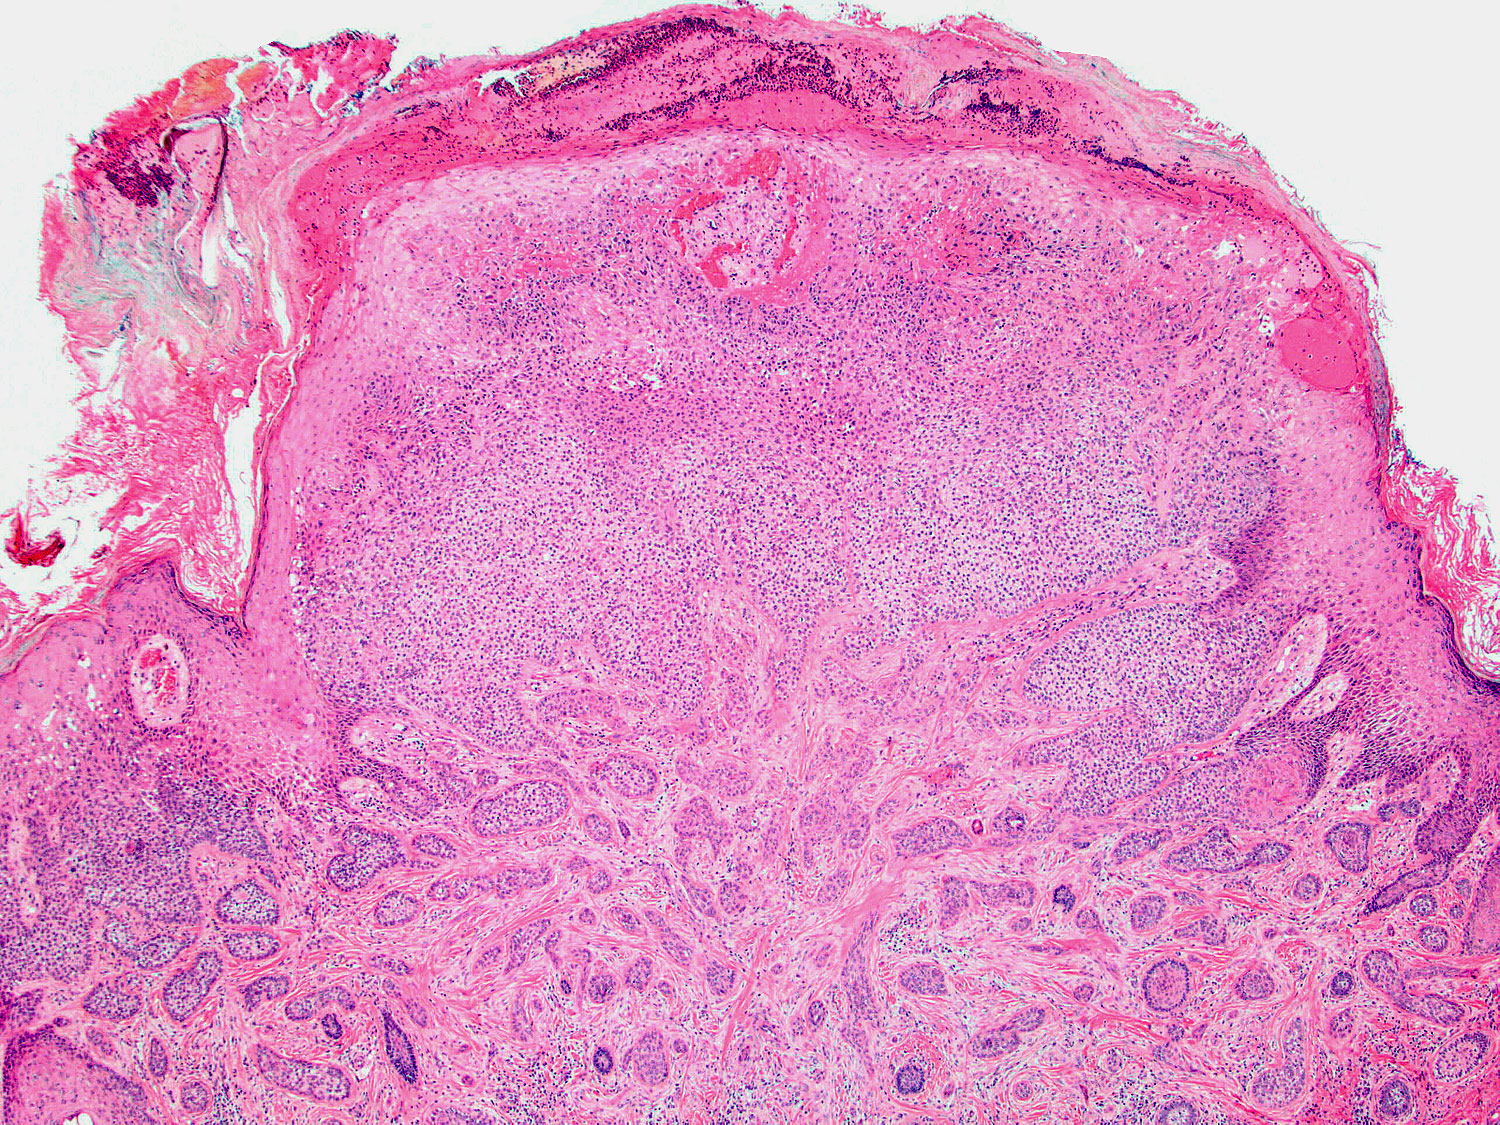

H&E staining (4x objective)